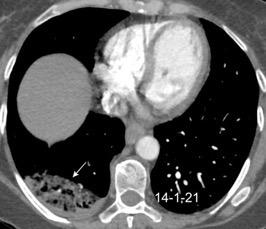

T. mixto de células germinales del testículo izquierdo

Nódulos pulmonares múltiples. (flechas verdes). Masas paratraqueales. (flechas amarillas). Dudoso ensanchamiento retrocrural (flechas negras). sigue….

T. mixto de células germinales del testículo

izquierdo Metástasis pulmonares. (flechas verdes). Ganglios paratraqueales. (flechas amarillas). Ganglios retroperitoneales (flechas negras)

Tawfik A et al. Trans-diaphragmatic Pathologies: Anatomical Background and Spread of Disease on cross-sectional Imaging. Current Problems in Diagnostic Radiology. 2021.